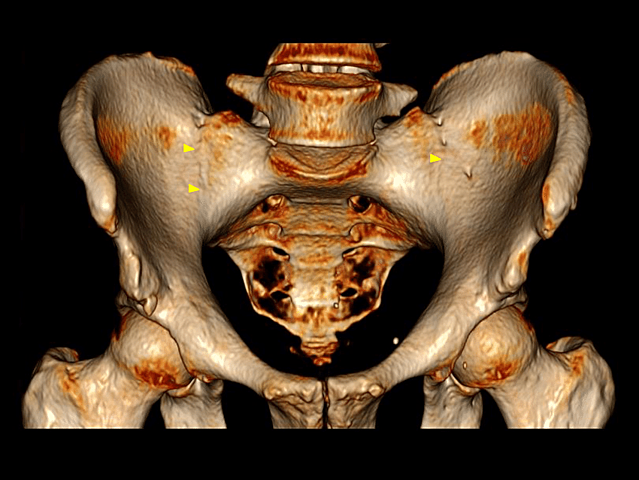

• Proyección de intensidad máxima

Proyección de intensidad máxima

a) Estructuras oseas se ven como lineas blancas.

b) Se proyecta cada vóxel con el mayor valor de atenuación en cada vista.

c) Visuliazacion de estructuras densas como vasos contrastados.